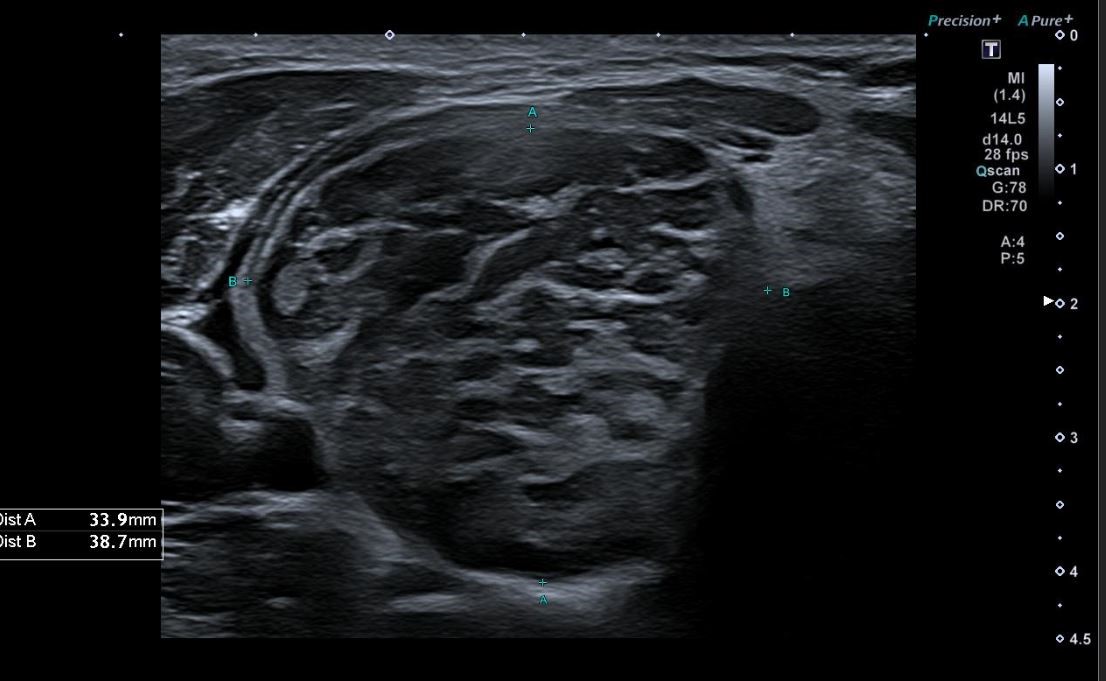

Una vez realizada la anamnesis y la exploración física, se decide realizar una ecografía clínica en la consulta, donde se objetiva un aumento difuso de tamaño del lóbulo tiroideo derecho (33,9 x 38,7 mm), levemente hipoecogénico, con áreas anecoicas en su interior y adenopatías asociadas. Se aplica Doppler color resultando positivo.